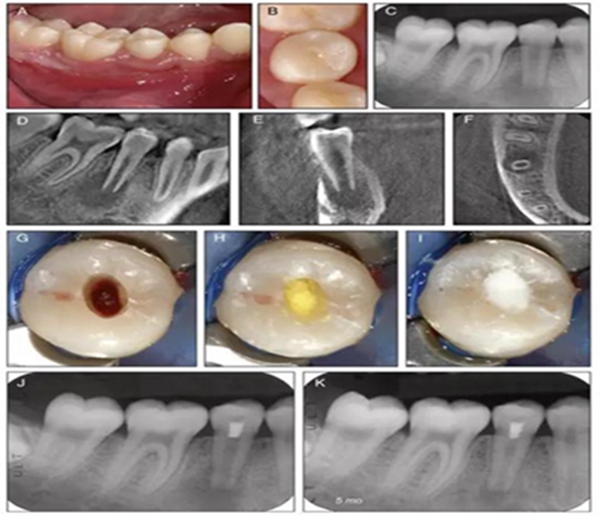

原則上年輕恒牙的牙髓治療應(yīng)盡可能以保存活髓的方式以便不影響牙根繼續(xù)發(fā)育。本文3個(gè)病例均描述了根尖尚未發(fā)育完成的下頜前磨牙被確診為牙髓壞死伴有大面積根尖病損,治療過程中在根管內(nèi)發(fā)現(xiàn)了部分活髓,而采用活髓切斷后都取得了很好的療效。